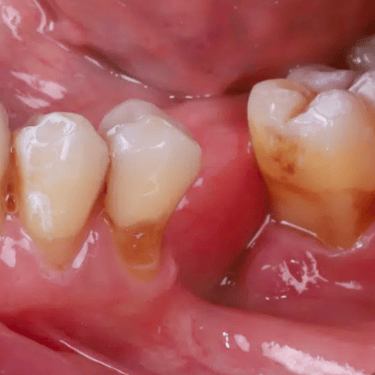

Pérdida de múltiples dientes

La pérdida de múltiples dientes es la ausencia de varios dientes que puede ser resultado de caries, enfermedades periodontales o traumatismos.

Los pacientes notan varios espacios vacíos en su boca, lo que afecta su capacidad para masticar y hablar adecuadamente.

El tratamiento incluye la colocación de varios implantes dentales para restaurar la función y la estética.